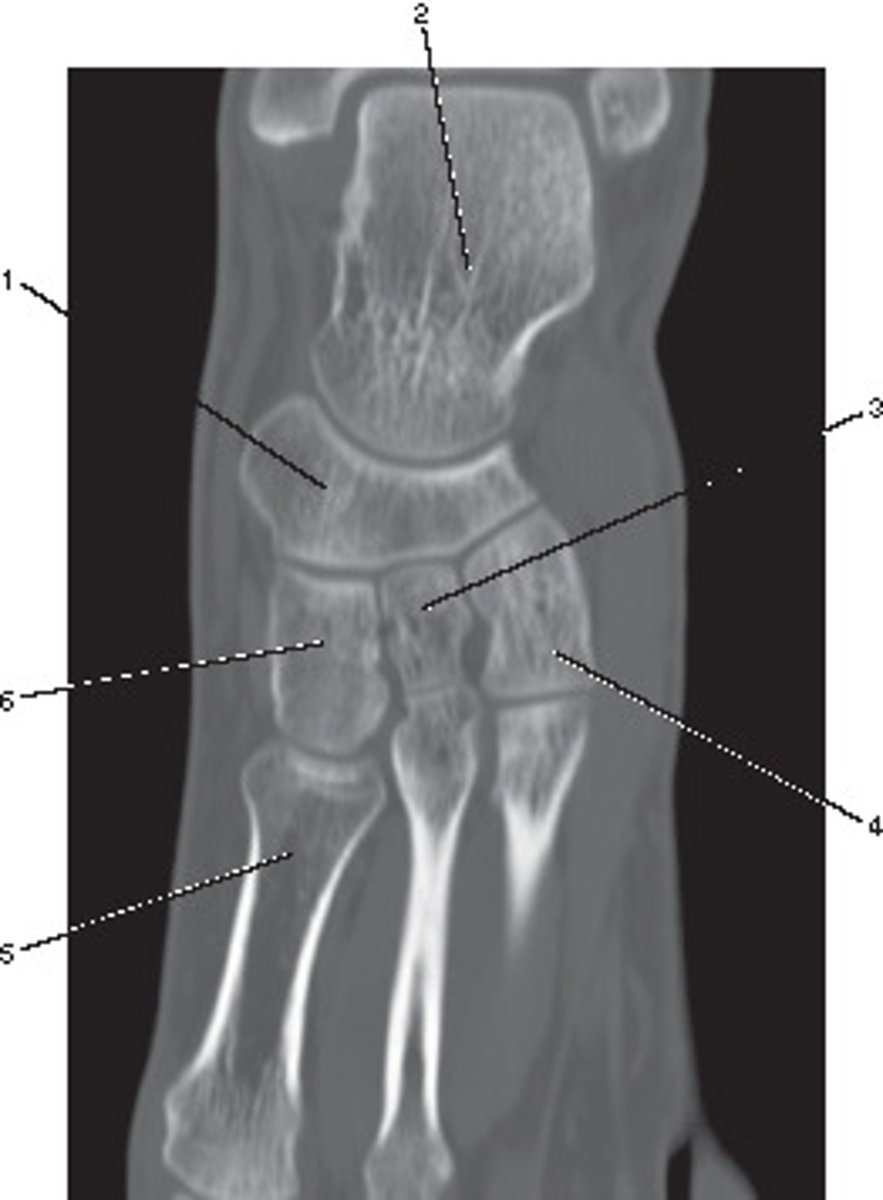

Sagittal

<p>What anatomic plane best describes this image</p>

Ulna

<p>Number 5 corresponds to which of the following?</p>